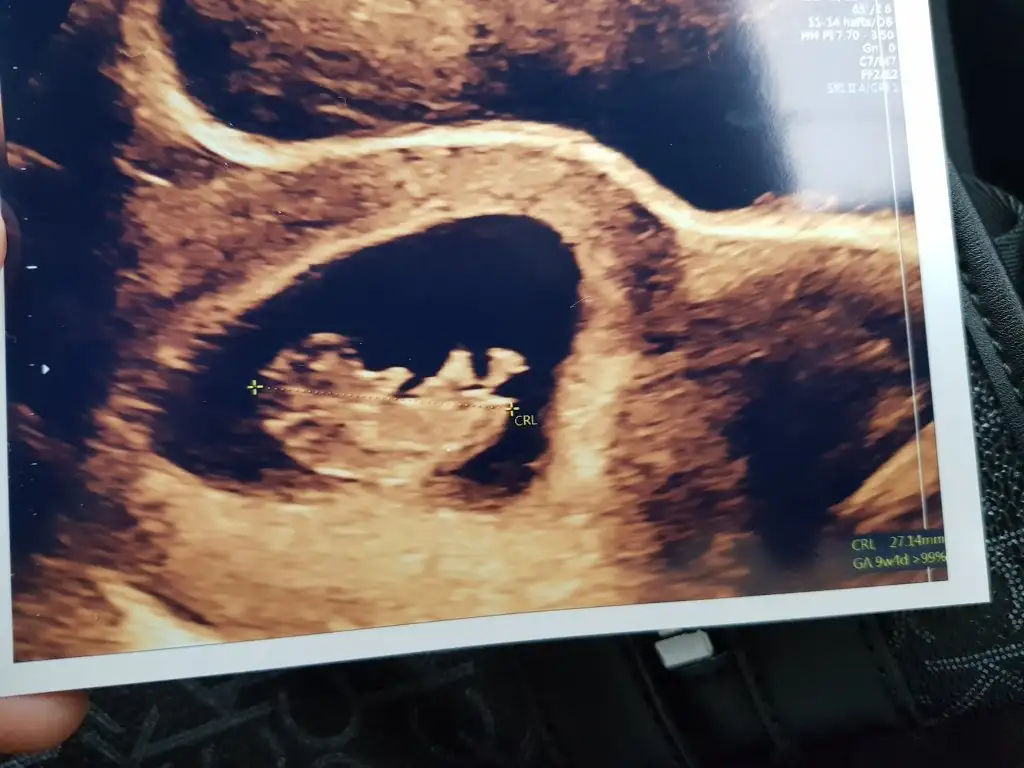

Kız gibi sanki 14 haftada nub olmaz ama sanki diklik olsa yada pipi olsa görünürdüEki Görüntüle 2703543 14 Haaftalık şuan nub a göre yorumlarmısınız